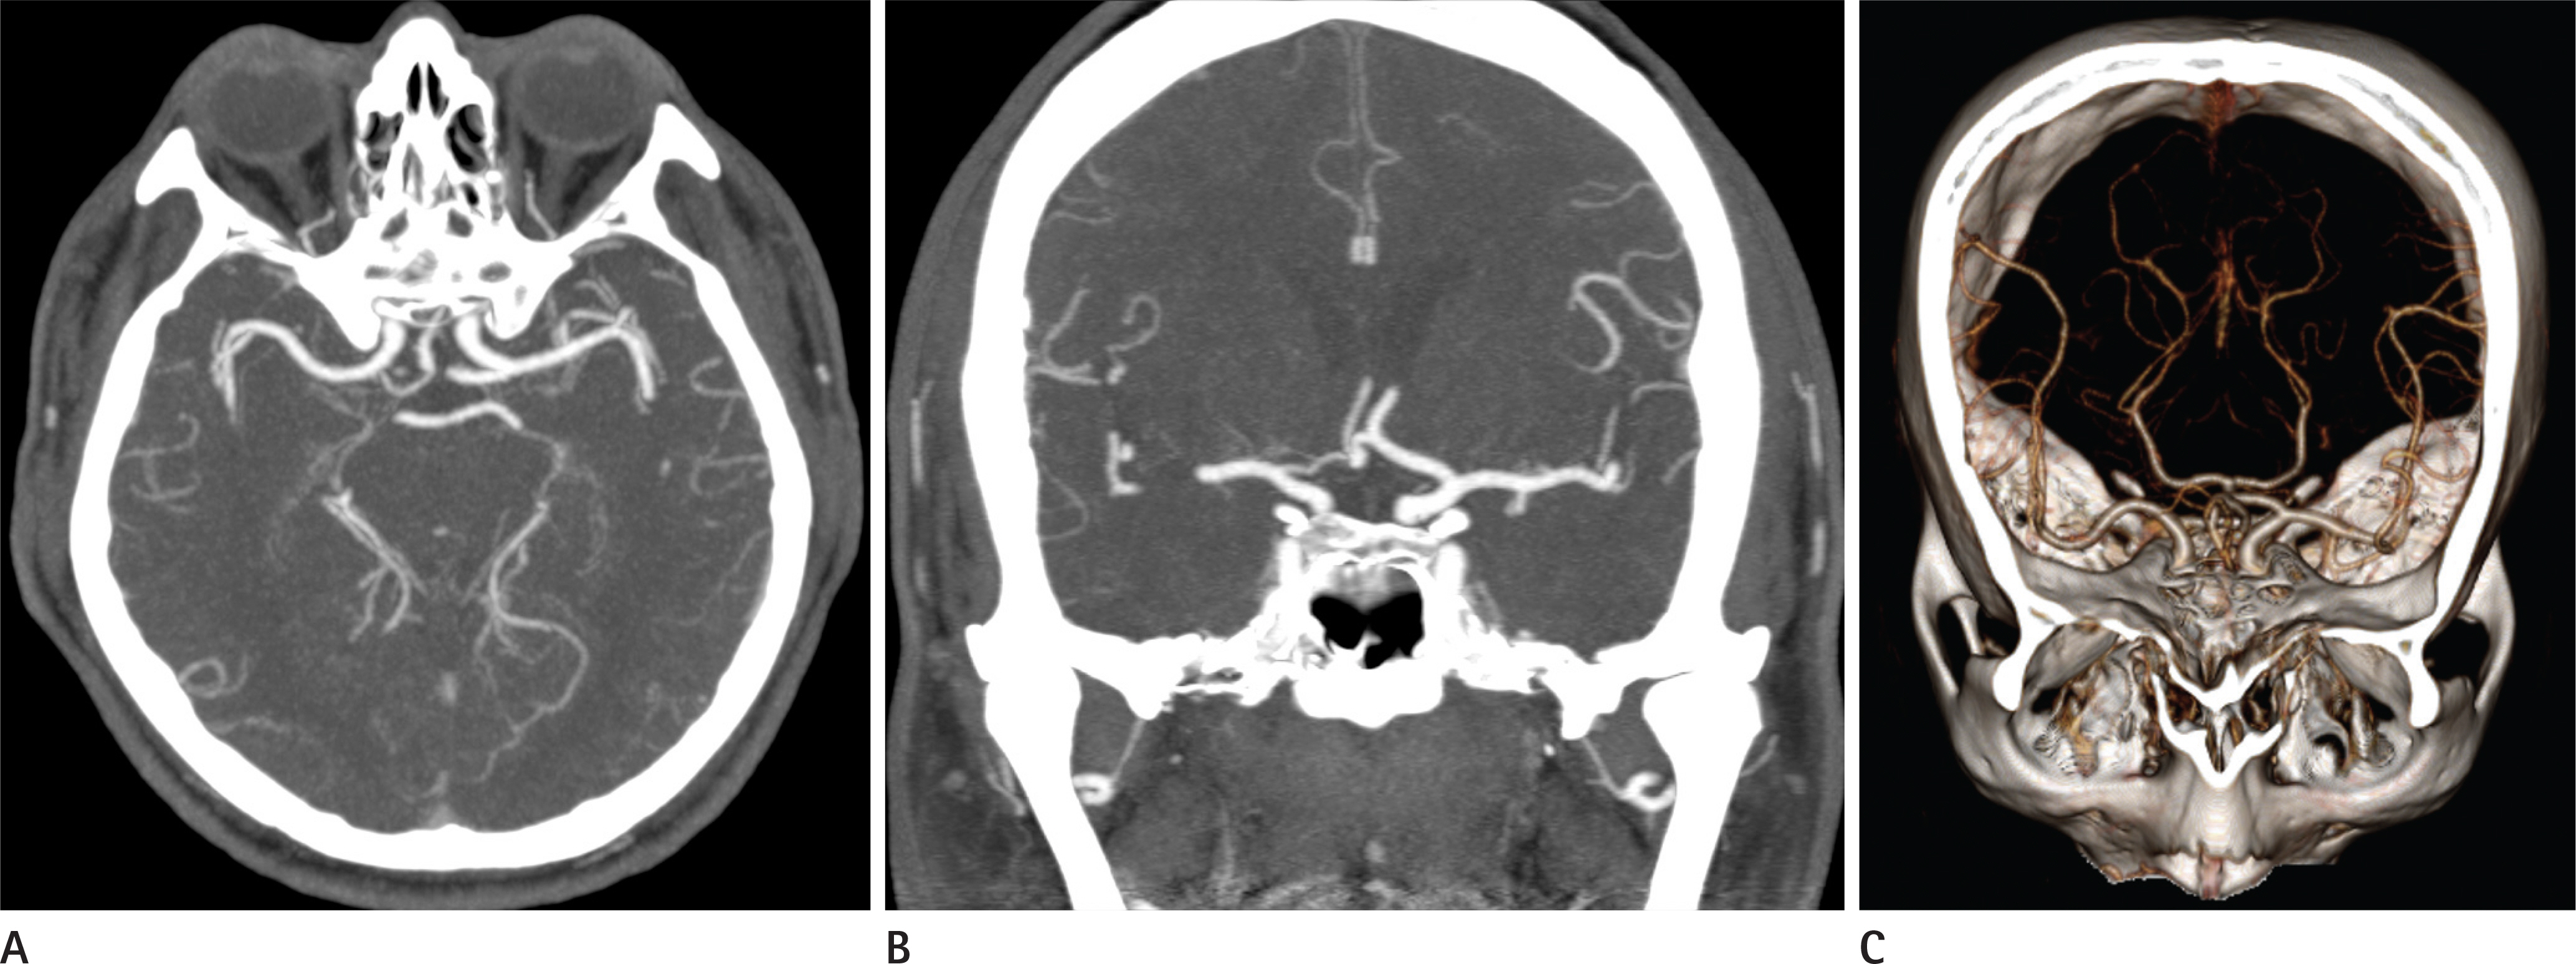

Attenuation-Based Automatic Tube Potential Selection in Cerebral Computed Tomography Angiography: Effects on Radiation Exposure and Image Quality

To investigate the feasibility of using the attenuation-based automatic tube potential selection (ATPS) algorithm for cerebral computed tomography angiography (CTA) and to assess radiation dose, vascular attenuation, and image quality compared to a conventional fixed 120-kVp protocol.

Among 36 volunteers for cerebral CTA, a total of 18 were scanned with fixed 120 kVp and 140 effective mAs using automatic tube current modulation. The other 18 were scanned with an ATPS algorithm. Radiation doses, attenuation, contrast-to-noise ratio (CNR) of the cerebral arteries, subjective scores for arterial attenuation, edge sharpness of the artery, visibility of small arteries, venous contamination, image noise, and overall image quality were compared between the groups.

The volume CT dose index and effective dose of the ATPS group were lower than those of the fixed 120-kVp group. The ATPS group had significantly higher arterial attenuation and no significant difference in CNR, compared with the fixed 120-kVp. The ATPS group had higher subjective scores for arterial attenuation, edge sharpness of the artery, visibility of small arteries, and overall image quality.

The ATPS algorithm for the cerebral CTA reduced radiation dose by 43% while maintaining image quality and improved the attenuation of cerebral arteries by selecting lower tube potential.